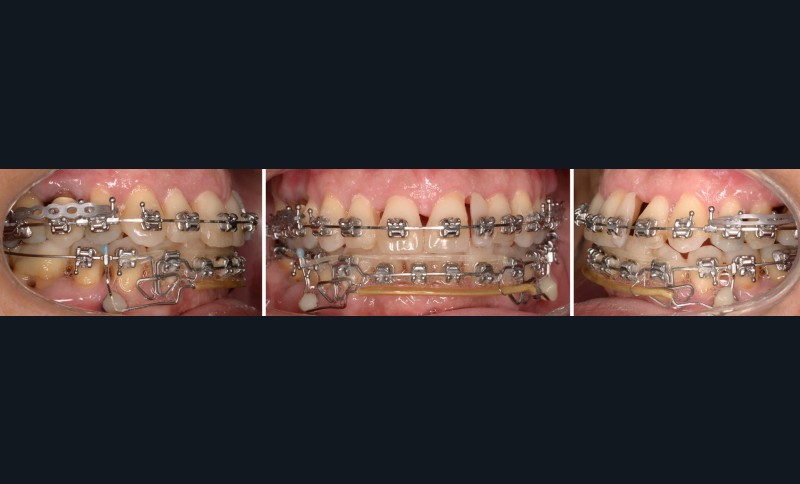

Une fois le surplomb augmenté, la fermeture maxillaire a été réalisée par une technique de glissement sur un arc acier .020x.025 à bouts arrondis.

Les objectifs sont atteints en 30 mois, la patiente est très satisfaite d’un point de vue fonctionnel et esthétique (fig. 10-13). La fonction linguale est rééduquée et la patiente continue sa maintenance parodontale régulière.

La durée de traitement a été longue et peut en partie être expliquée par la perte des premières minivis ayant entraîné une temporisation de 4 mois pour permettre la cicatrisation osseuse et l’acceptation par la patiente d’une nouvelle pose de minivis. La fermeture des diastèmes maxillaires ne pouvait être entreprise que dans un deuxième temps, car elle nécessitait d’abord l’ingression des incisives mandibulaires afin de retrouver du surplomb. Une suspension temporaire des déplacements maxillaires a aussi été réalisée pendant quelques mois à la suite de la réapparition de poches au niveau des molaires maxillaires.